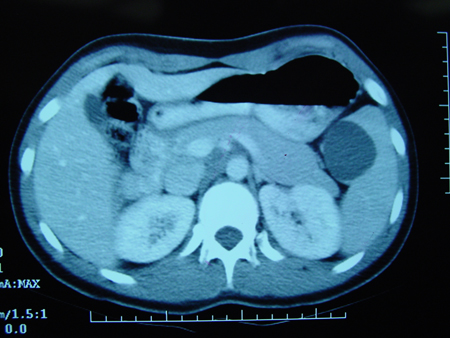

CT scan of teenage girl presenting with mid-epigastric abdominal pain as a result of gallstone pancreatitis. The large fluid collection in the pancreatic bed (white arrow) and lack of pancreatic enhancement suggest liquefactive necrosis of the pancreas

From the collection of Dr Kuojen Tsao; used with permission